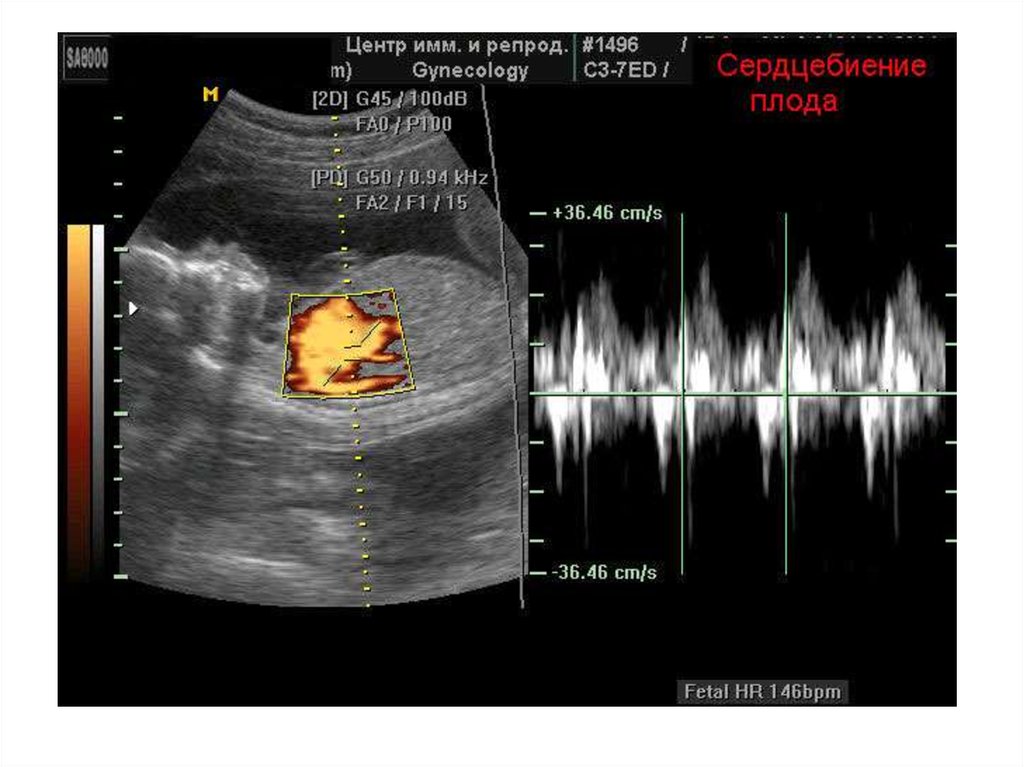

УЗИ: окно в мир эмбриона

УЗИ — это как подводная лодка с перископом, позволяющая заглянуть в таинственный мир внутриутробного развития. На ранних сроках беременности врачи используют трансвагинальное УЗИ — оно дает более четкую картинку, чем обычное. Представьте себе, что вы смотрите на крошечный экран, где пульсирующая точка размером с маковое зернышко — это и есть сердце вашего будущего малыша.

Но что если этой пульсации нет? Тут-то и начинается детективная работа врача. Он оценивает размер эмбриона, наличие желточного мешка, его форму. Все эти детали — как кусочки пазла, которые нужно сложить воедино, чтобы получить полную картину.

Не пренебрегайте и УЗИ-диагностикой. Первое УЗИ обычно проводят на 6-8 неделе беременности. Именно в это время можно увидеть сердцебиение плода. Если же на УЗИ в 10 недель нет сердцебиения, это может быть признаком замершей беременности. Но не стоит делать поспешных выводов – только врач может поставить окончательный диагноз.